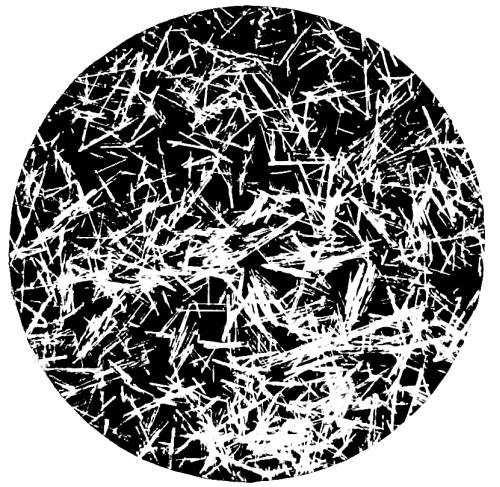

40. Photo-micrograph of Crystals of Strychnine Sulphate from an Aqueous Solution 389

41. Photo-micrograph of Crystal of Strychnine Sulphate from Aqueous Solution 389

42. Photo-micrograph of Strychnine Sulphate, Film Preparation from Chloroform Solution 391

43. Photo-micrograph of Chromate of Strychnine 391

44. Photo-micrograph of Sulphocyanate of Strychnine 392

45. Photo-micrograph of Crystals of Brucine Sulphate 395

46. Photo-micrograph of Crystals of Brucine Sulphate 395